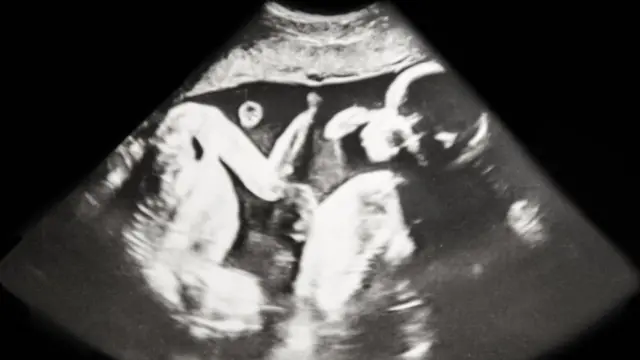

Si un gemelo desaparece antes de las 12 semanas, es poco probable que la madre lo sepa porque las ecografías rara vez se realizan tan pronto.

"En términos médicos, se llama 'síndrome del gemelo desaparecido' porque en una ecografía temprana hay dos latidos del corazón, pero luego uno de ellos parece desaparecer", dice van Dongen.